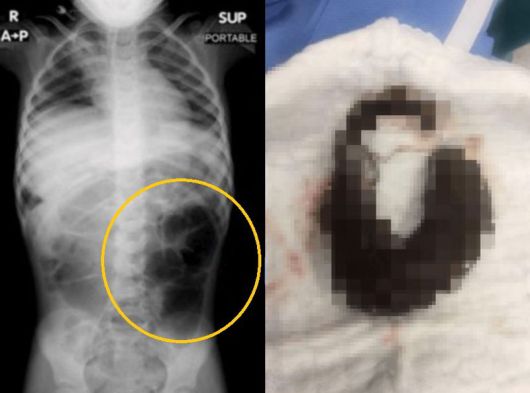

복통을 호소하던 6세 여아의 뱃속에서 머리카락 덩어리가 발견됐다. 사진=큐레우스저널 |

22일 큐레우스 저널에 따르면 사우디아라비아에서 6세 여아가 복통과 지속적인 소화 불량을 호소해 검사를 받은 결과 위장 내 큰 이물질이 발견됐다.

수술 결과 위에서 나온 이물질의 정체는 바로 머리카락 덩어리였다. 머리카락 덩어리는 위에서 소장까지 길게 이어진 모습이었다.